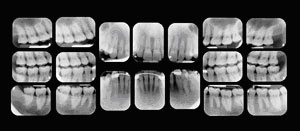

This visit to the doctor typically includes an x-ray that allows the doctor to view the structure of the jaw, the position of any teeth that have not yet erupted, malformed roots, and tooth decay.